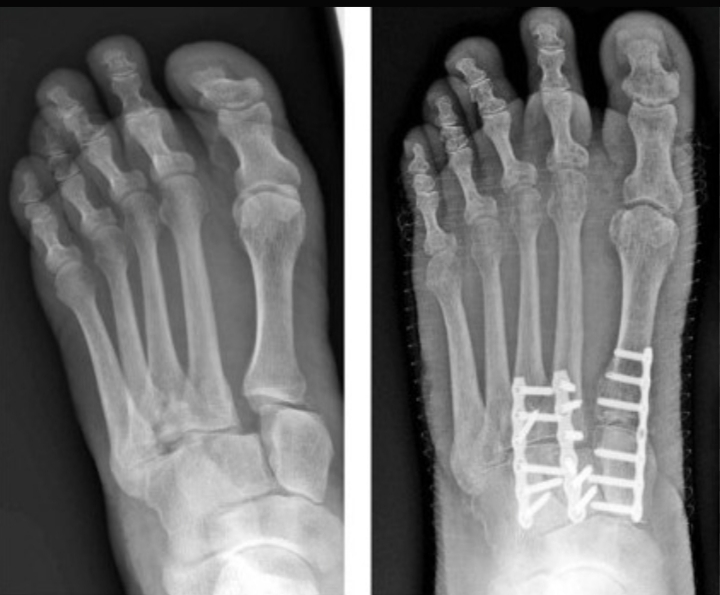

- X-rays, sometimes taken while standing

- Realignment of displaced bones

- Fixation using screws or plates